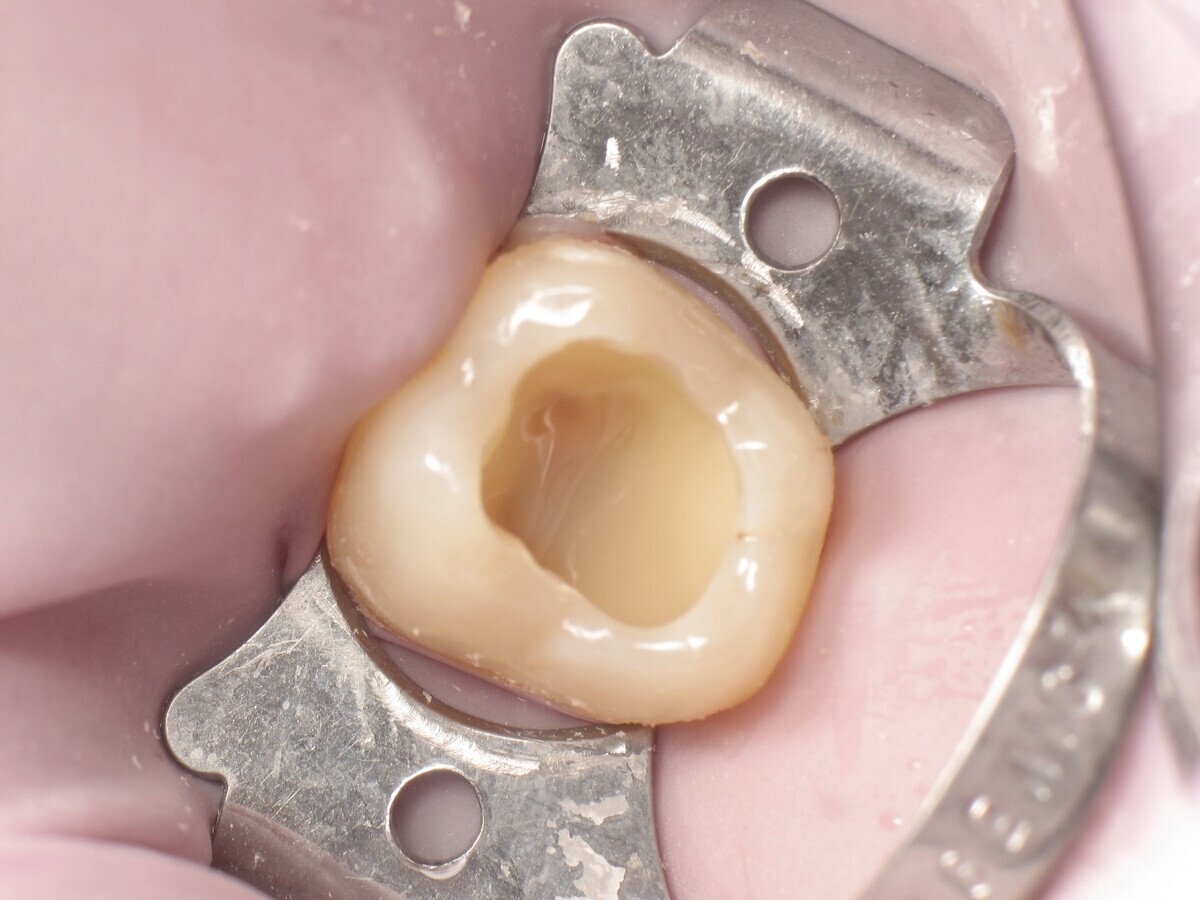

La secuencia fotográfica muestra la cavidad después de la aplicación y fotopolimerización del adhesivo y el modelado que se obtiene con el composite termoviscoso. Fotos: Yassine HARICHANE

Este artículo describe el tratamiento de una cavidad clase I en un molar utilizando un composite termoviscoso mediante la técnica de la almohadilla (Figura 1). En primer lugar, se registran los detalles anatómicos utilizando una resina transparente, fluida y fotopolimerizable (Clip Flow, VOCO). El diente se aísla con un dique antes de aplicar el composite transparente a la superficie oclusal con un cepillo aplicador y fotopolimerizar durante 10 segundos (Figuras 2-4). La almohadilla oclusal así obtenida (Figura 5) debe almacenarse en alcohol (etanol o isopropanol) para eliminar la capa de inhibición. Luego se limpia la cavidad clase I (Figuras 6 y 7). A continuación se graba el esmalte durante 30 segundos y la dentina durante 15 segundos (Conditioner 36, Dentsply Sirona) y luego se enjuaga bien (Figuras 8 a 10). Debido al bajo espesor de la dentina remanente, también se aplica protección pulpar (Telio Desensitizer, Ivoclar Vivadent) (Figura 11). Luego se frota el adhesivo sobre las superficies dentales durante 20 segundos (Futurabond DC, VOCO), luego se seca bajo una pulverización de aire sin aceite graso durante 5 segundos y luego se fotopolimeriza durante 10 segundos (Figuras 12, 13). Para una humectación óptima, el fondo de la cavidad se cubre con un compuesto fluido de baja viscosidad (GrandioSO Light Flow, A3.5, VOCO) y se fotopolimeriza durante 20 segundos (Figuras 14, 15). Utilizando el Dispensador VisCalor, un dispensador portátil que permite el calentamiento y la aplicación simultánea de resinas, la cavidad se llena luego con un composite termoviscoso bulk (VisCalor Bulk, A2, VOCO).

El composite calentado tiene una consistencia fluida para un perfecto manejo y se puede aplicar en capas de hasta 4 mm (Figura 16). A medida que se enfría hasta la temperatura corporal, la viscosidad del composite termoviscoso aumenta, lo que lo hace muy fácil de modelar (Figura 17). Finalmente, se realiza la fotopolimerización durante 20 segundos (potencia ≥ 1.000 mW/cm2, Figura 18). El uso de un composite bulk permite un llenado rápido en un solo paso. Si se requiere una segunda capa, la capa superior también se puede realizar con composite termoviscoso estético universal VisCalor en color A1 (VisCalor, VOCO, Figura 19), que se fotopolimeriza en incrementos de 2 mm. La consistencia innovadora del composite termoviscoso permite una reproducción fácil de la anatomía y una eliminación fácil del exceso de material (Figura 20) [Ilie et al. 2014]. A continuación se aplica la almohadilla oclusal creada previamente (Figura 21). La fotopolimerización se realiza primero con la almohadilla y luego sin durante 20 segundos cada una (Figuras 22 a 24). No se requiere material separador entre el material compuesto y la almohadilla. Debido a la eliminación previa de la capa de inhibición de la almohadilla, hay muy pocos o ningún punto de contacto, de modo que no se puede crear ningún enlace químico real entre la almohadilla y la resina. Los pocos puntos de contacto presentes solo significan que puede sentir una ligera resistencia cuando se retira la almohadilla después del primer ciclo de fotopolimerización.

Figura 21. Aplicación de la almohadilla oclusal.

Figura 22. Polimerización ligera con la almohadilla oclusal.